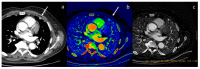

Dual-energy computed tomography (DECT) is one of the most promising technological innovations made in the field of imaging in recent years. Thanks to its ability to provide quantitative and reproducible data, and to improve radiologists' confidence, especially in the less experienced, its applications are increasing in number and variety. In thoracic diseases, DECT is able to provide well-known benefits, although many recent articles have sought to investigate new perspectives. This narrative review aims to provide the reader with an overview of the applications and advantages of DECT in thoracic diseases, focusing on the most recent innovations. The research process was conducted on the databases of Pubmed and Cochrane. The article is organized according to the anatomical district: the review will focus on pleural, lung parenchymal, breast, mediastinal, lymph nodes, vascular and skeletal applications of DECT. In conclusion, considering the new potential applications and the evidence reported in the latest papers, DECT is progressively entering the daily practice of radiologists, and by reading this simple narrative review, every radiologist will know the state of the art of DECT in thoracic diseases.